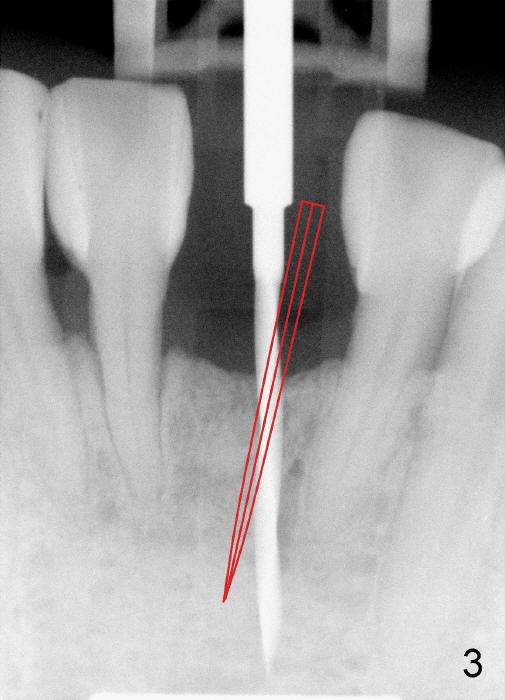

A 3x17 mm one piece implant is planned.  Osteotomy is created by a 1.5 mm pilot drill at the depth of 14 mm without incision (Fig.2); it is close to a neighboring incisor.  The trajectory of the osteotomy is intended to be changed (Fig.3 red) without success (white, 17 mm deep).  With measurement and calculation, the 3x17 mm implant is not expected to touch the root of the adjoining tooth.  In fact it is fine with insertion torque between 50-60 Ncm (Fig.4).  Without incision, the papillae appear to form immediately following implantation (Fig.5).  With adjustment of the abutment (Fig.6), an immediate provisional is fabricated (Fig.7).

To place the implant correctly, the preop PA should be studied carefully to find the divergence of the roots of the neighboring teeth (Fig.1).  The depth of the initial osteotomy should be shorter, for example, 11 mm instead of 14 mm.  Once the trajectory is found to be corrected, an incision should be made; the osteotomy is to be overcorrected with Lindermann bur (Fig.8 black); the whole osteotomy is changed with proper angulation (Fig.9 arrows).